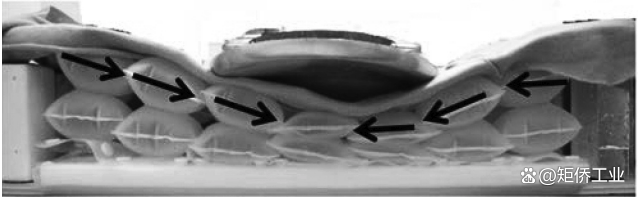

两个气囊气囊的尺寸为80 x 80毫米,垂直行程约100毫米。该结构设计用于通过中间的狭窄部分释放横向(剪切)力。如图4所示,每个气囊气囊向负载中心振动,使身体沉浸在床垫中。传统床垫使用相对较大的气囊气囊,剪切应变或应力往往直接传递到患者的皮肤,这可能增加压力性溃疡的风险。我们的双气囊气囊系统有效地减少了剪切应力。